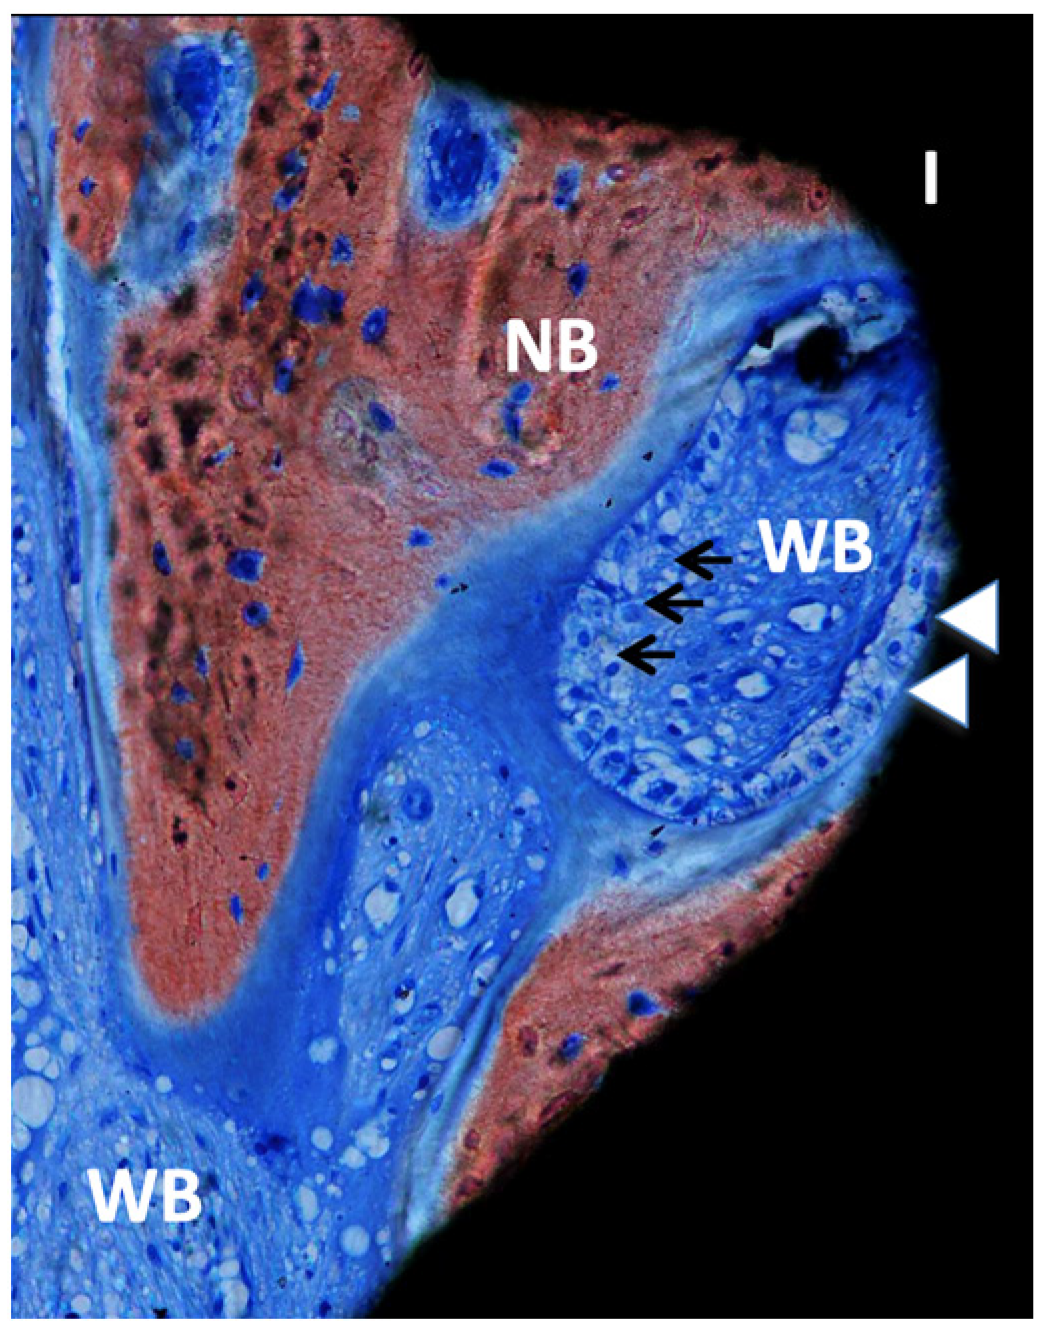

3. Results